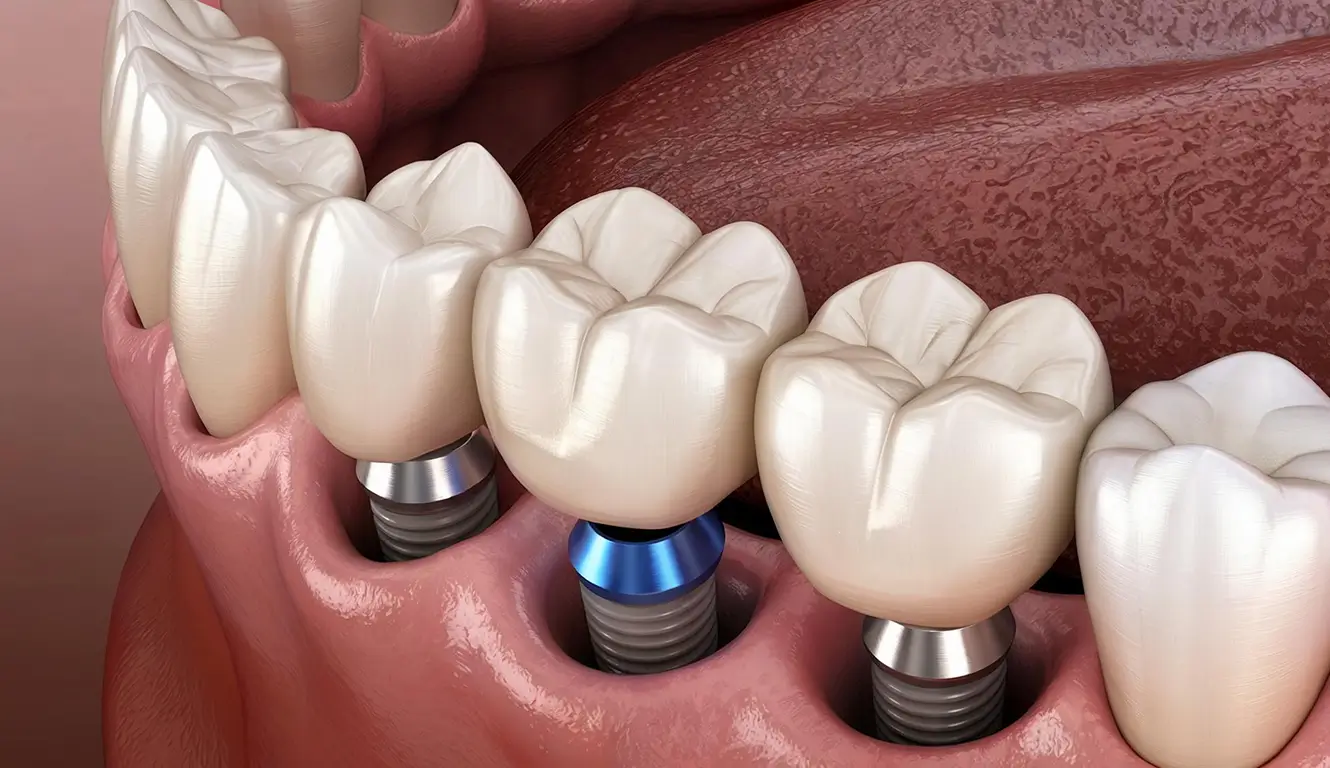

Multiple teeth Dental implants provide several advantages over other teeth replacement options. In addition to looking and functioning like natural teeth, implant-supported bridges replace teeth without support from adjacent natural teeth.

Once a tooth is lost, it can’t be replaced naturally, but modern dentistry allows you to fill the gap using implants that support a dental bridge.

Our team of experts will develop custom fabricated crowns and are placed over the abutments and will function like a real tooth. You don’t have to worry about the future bone loss or difficulty in chewing your favorite food.